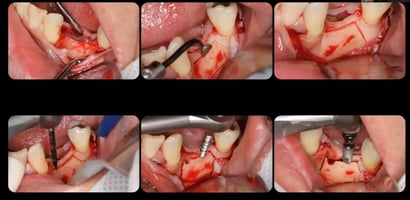

Casos Avançados: A Prática Comprovando a Teoria

Os casos clínicos apresentados demonstram com clareza a capacidade das tecnologias digitais de transformar cirurgias complexas em procedimentos mais previsíveis.

Foi demonstrado, por exemplo:

• Recobrimento radicular associado a implante imediato, com uso simultâneo da guia para permitir uma execução flapless e, ao mesmo tempo, viabilizar um retalho avançado de Zucchelli.

• Correção de extremo livre com guia mucosuportada, usando pinos de fixação para garantir estabilidade.

• Implante imediato com carga realizada a partir de extração flapless guiada, permitindo controle do envelope ósseo.

Esses exemplos reforçam que a tecnologia não elimina a necessidade de habilidade, mas expande as possibilidades do cirurgião experiente.

Biomateriais e Fluxo Digital

O biomaterial apresentado, The Graft Collagen, mostra como a integração entre biologia e tecnologia é fundamental. O material possui excelente moldabilidade, partículas pequenas e boa integração, sendo eficiente para:

• Preenchimento de gaps periimplantares

• Regeneração óssea guiada

• Preservação alveolar

Junto ao planejamento e execução guiada, ele compõe um fluxo digital-biológico coeso e eficiente.